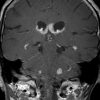

Lymphoma

» Thông tin: Nữam giới – 60 tuổi.

» Lâm sàng: Rối loạn tri giác.